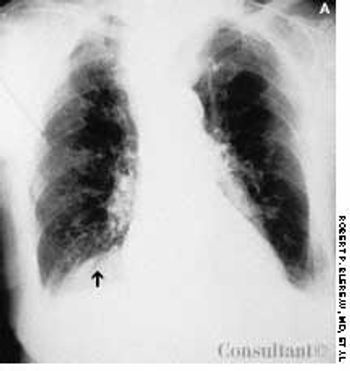

A 95-year-old woman was brought to the emergency department with hemoptysis. Erect posterior-anterior (A) and lateral (B) chest films showed a density at the base of the right lung posteriorly. A CT scan (C) revealed that the mass was the right kidney above the diaphragm and adjacent to the heart. The kidney had migrated through a foramen of Bochdalek.